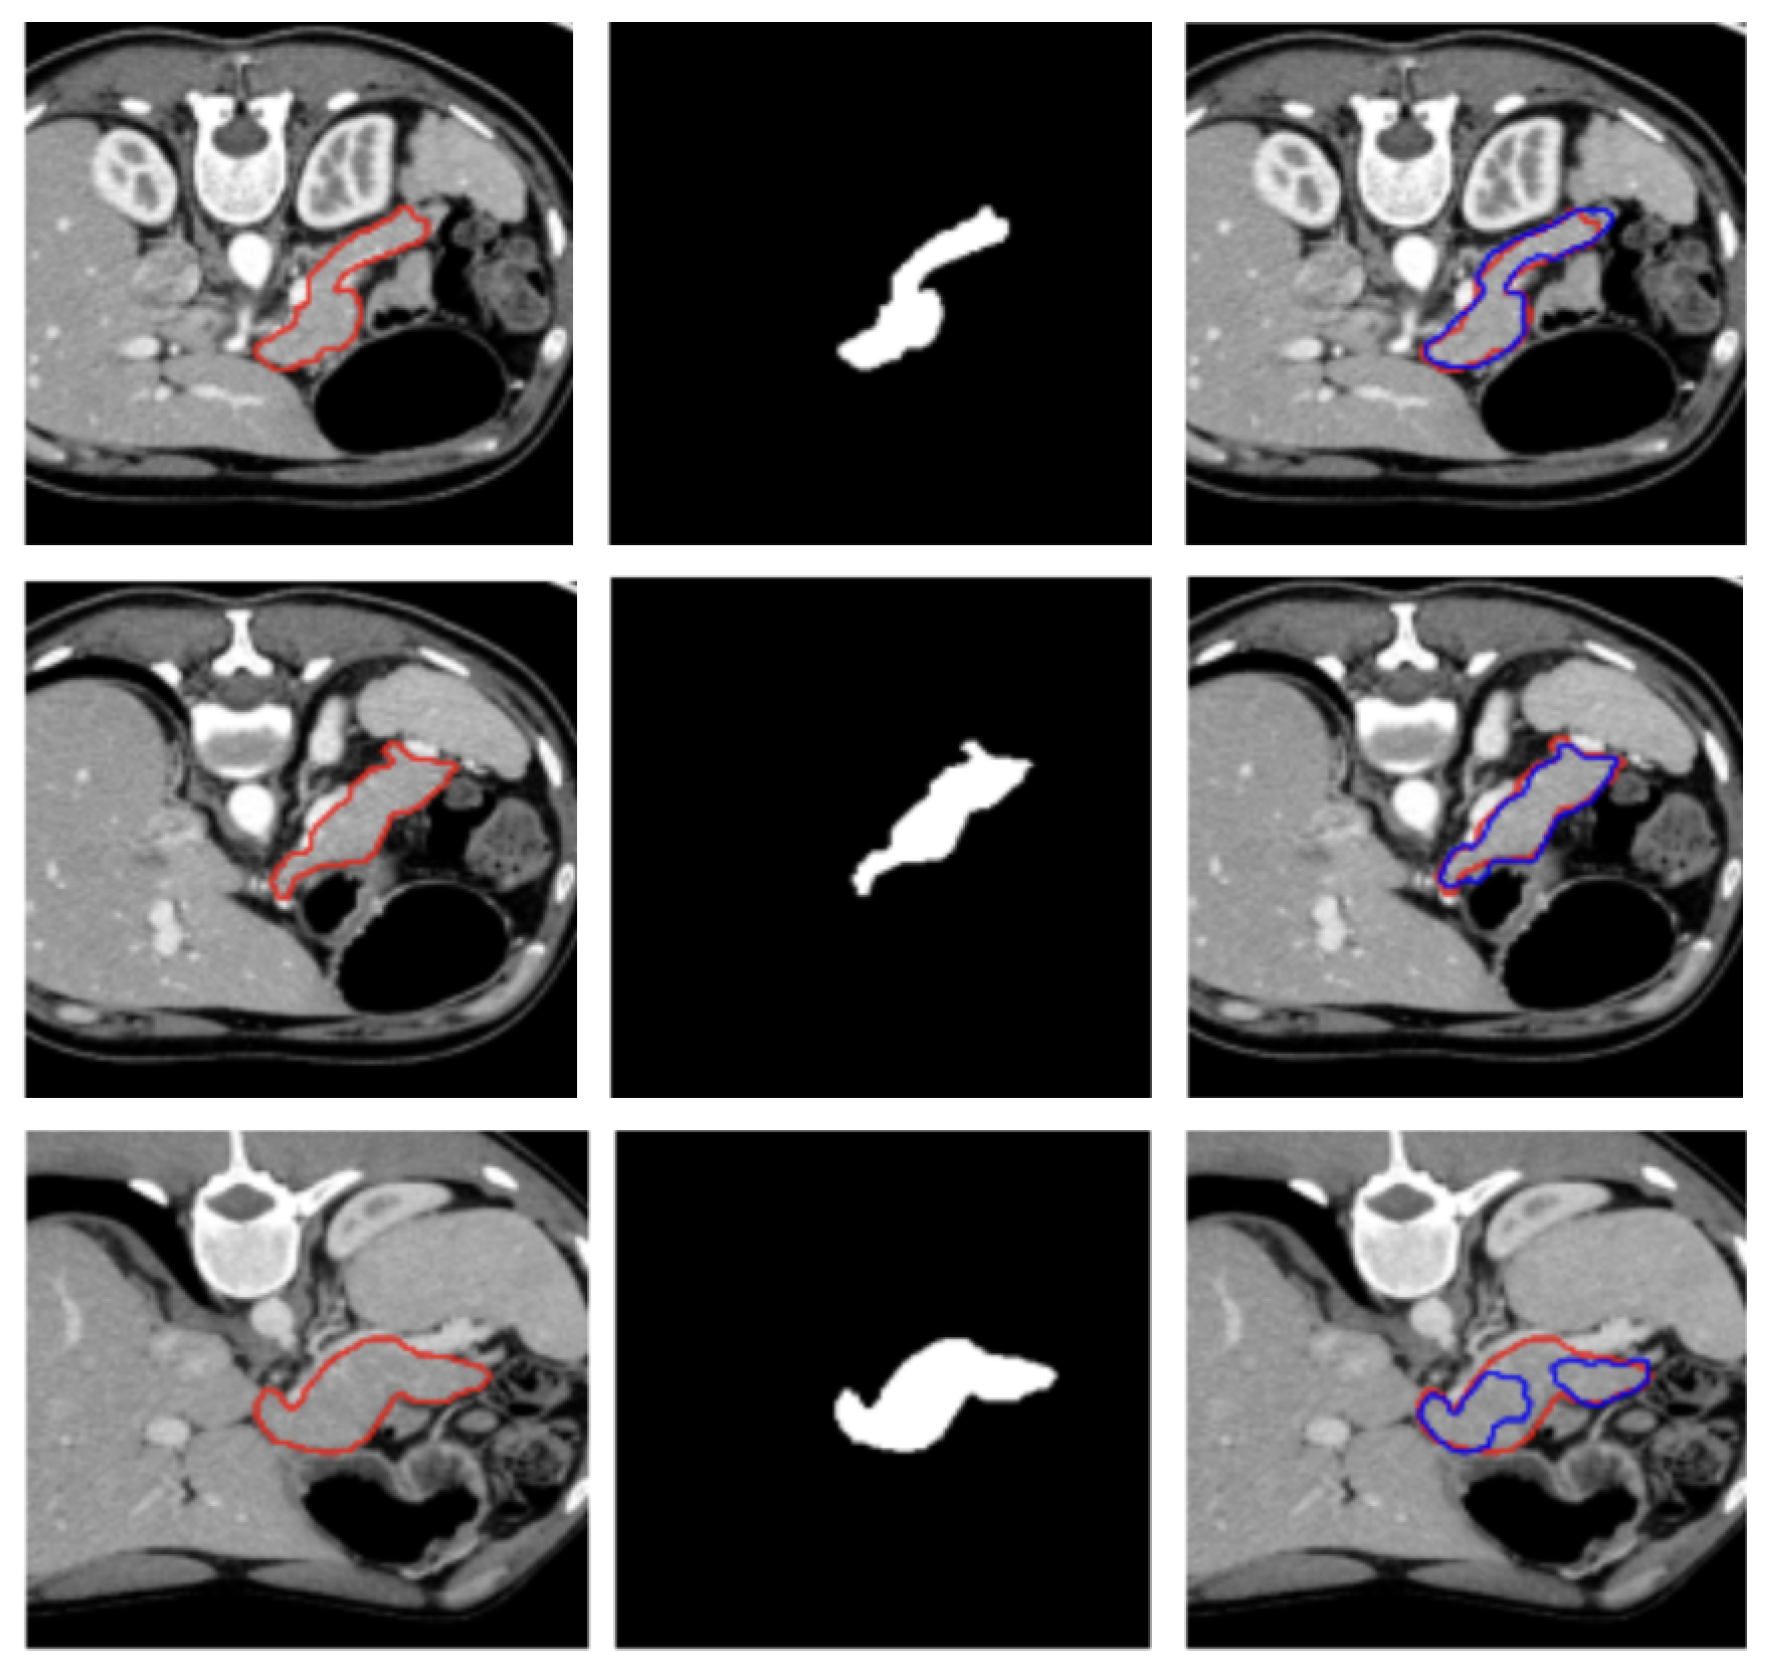

Three examples of segmentation obtained on test samples of the MSD dataset are illustrated in Figure 3.

Figure 3.

Visualization of two representative test samples from the MSD dataset showing: the input image with the pancreas ground truth overlaid as a red contour (left), the corresponding pancreas mask (center), and the output of the model overlaid to the input image as a blue contour (right). The first sample (first and second row) illustrates an easy case with clear organ boundaries and the second sample (bottom row) depicts a more challenging case with low contrast, yet the model still captures the main structure.

Figure 2 and Figure 3 show, qualitatively, the results of our attention-based 3D U-Net model trained on NIH and MSD datasets, respectively, with a combined Focal and Dice loss. The figures show across different sample cases, how the model successfully delineates the pancreas with high spatial accuracy, as demonstrated by the strong alignment between predicted and ground truth contours. The use of Dice loss contributed to the precise overlap in the segmented regions, while Focal loss improved the model sensitivity to challenging areas, especially along class boundaries where the pancreas is thin or adjacent to low-contrast structures. Notably, even in slices where the pancreas is partially obscured or appears small and fragmented, the model maintains accurate contour predictions. This suggests that the attention mechanism effectively focuses on relevant anatomical regions, suppressing background noise and enhancing feature discrimination.

These visual results support the quantitative performance of the model reported in Table 1 and Table 2 and demonstrate its ability to produce reliable and anatomically consistent pancreas segmentation in volumetric CT data.